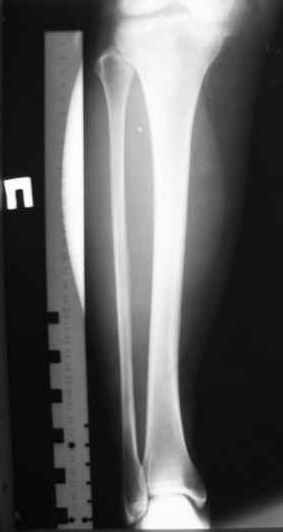

Для определения длинны и диаметра стержня использовали линейку-шаблон, позволяющей с легкостью рассчитать длину и диаметр стержня с проекцинно искаженными размерами, как конечности, так и линейки-шаблона.

Клинический пример:

Больная Я. 45 лет, пострадала в результате случайного падения на улице 19.12.2005., имеет место открытый 1 степени перелом обеих костей левой голени со смещением отломков.

произведена закрытая репозиция перелома с последующим введением стержня (на данном этапе производился рентген-контроль)

Убедившись в достаточной репозиции перелома, произведено дистальное и проксимальное блокирование интрамедуллярного стержня.